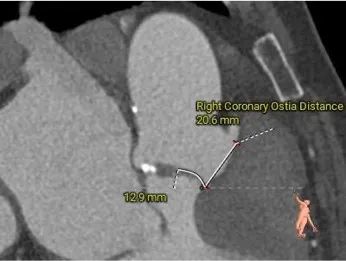

左冠15.7,右冠19.4,综合分析冠脉阻挡风险适中

• 左、右冠高度可,切线位测量,无冗长瓣叶,结合瓦氏窦、STJ 内径综合预估,冠脉阻塞风险适中